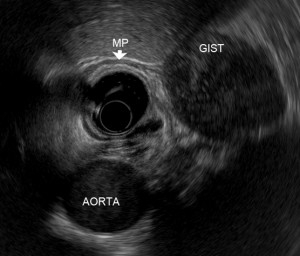

Endoscopic ultrasound (EUS) is an advanced endoscopic procedure specialized for the evaluation of various benign and malignant diseases involving the gastrointestinal tract and pancreatobiliary system using an ultrasound probe equipped on a flexible endoscope. Depending on the disease condition being evaluated, an EUS procedure usually takes about 20 to 40 minutes. Common conditions that can benefit from EUS are listed below (Table 1).

With its high resolution imaging, EUS can provide important information for local staging in patients with suspected gastrointestinal or pancreatobiliary tumours. When histological diagnosis is needed, EUS guided Fine Needle Aspiration (EUS-FNA) is a valuable technique for specimen acquisition. In addition to diagnostic evaluation, EUS can also be therapeutic. For example, in patients with chronic pain from pancreatic cancer, EUS guided Celiac Plexus Neurolysis (EUS-CPN) can provide effective palliation of cancer related pain, improving quality of life.

- Upper gastrointestinal tract submucosal tumors